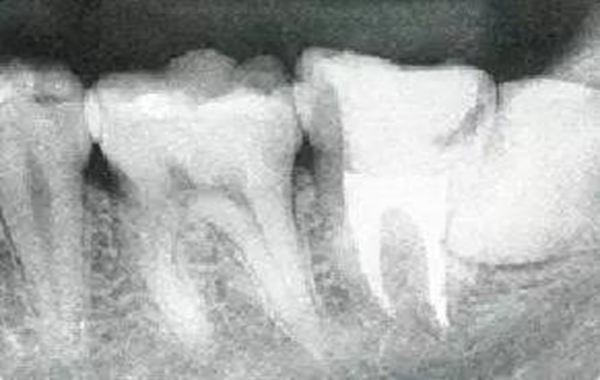

●參考病例① 35歲女性

35歲女性。妊娠4個(gè)月。過(guò)去雖然接受過(guò)刷牙指導(dǎo),但菌斑控制狀態(tài)依然不理想?;颊哂邪l(fā)現(xiàn)自己刷牙時(shí)牙齦出血。

●參考病例② 25歲女性

25歲女性。菌斑控制狀態(tài)不好。齦溝除磨牙處外全在3mm以下,X光照片上左上、右下、左下的第一磨牙上有垂直性骨吸收。這個(gè)病例是參考病例①10年前的狀態(tài),是典型的侵襲性牙周炎局部型。

牙周病的發(fā)展因部位不同而發(fā)展程度不同的。10點(diǎn)后的狀態(tài)參考病例①和參考病例②的磨牙處的狀態(tài)相比較,思考下沒(méi)接受治療病情發(fā)展的特別性吧。

參考病例① 35歲女性

在左下第一磨牙在25歲時(shí)近中處可以看到垂直性的骨吸收,但35歲時(shí)吸收停止,原本沒(méi)有見(jiàn)到的遠(yuǎn)中處骨吸收的,現(xiàn)在卻吸收得很嚴(yán)重。

在右下處,原本有大量骨吸收的第一磨牙處的吸收卻變緩慢,原本沒(méi)有吸收的第二前磨牙卻出現(xiàn)了吸收。出現(xiàn)吸收的左上第一磨牙的遠(yuǎn)中處,吸收得越來(lái)越多了。